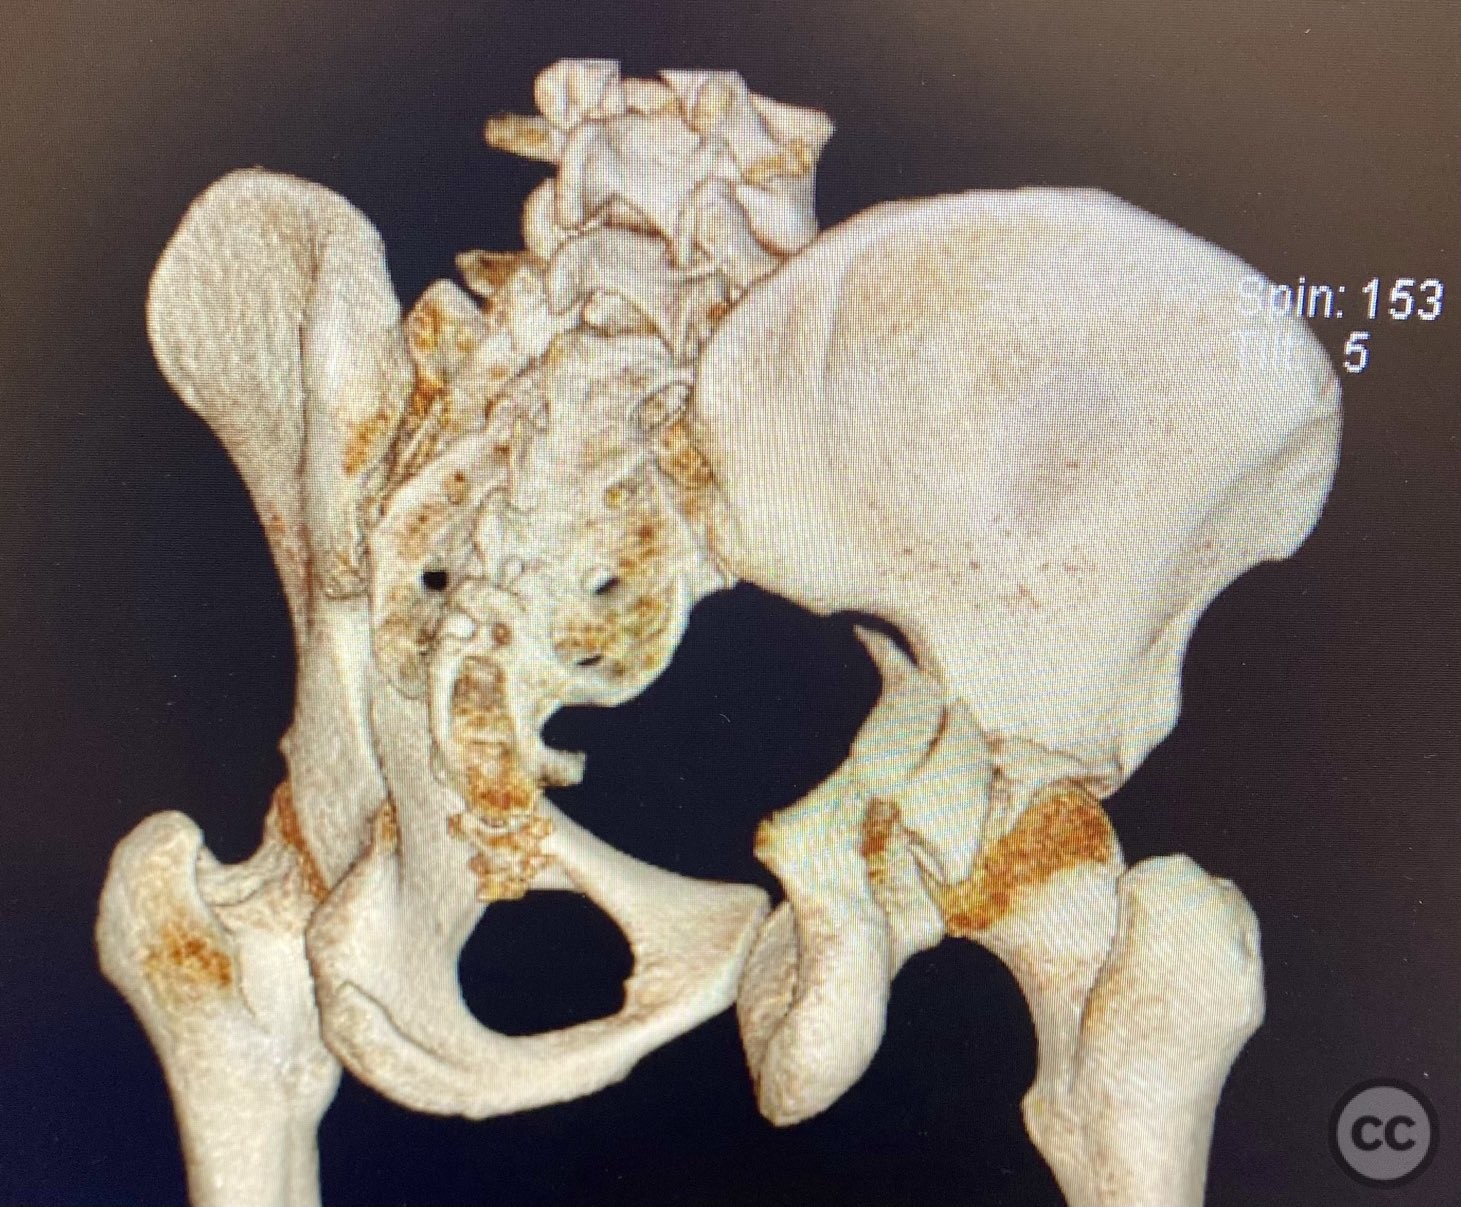

Clinical Details

Clinical and radiological findings:  A patient sustained a comminuted posterior wall acetabular fracture-dislocation (AO/OTA 62-B1.3) involving the greater sciatic notch, with associated traumatic sciatic nerve injury. Following closed reduction, imaging demonstrated an intra-articular fragment located within the acetabular fossa (fossa acetabuli). Clinical examination revealed neurological deficit consistent with sciatic nerve involvement. Radiographs and CT confirmed the extent of comminution and intra-articular displacement.